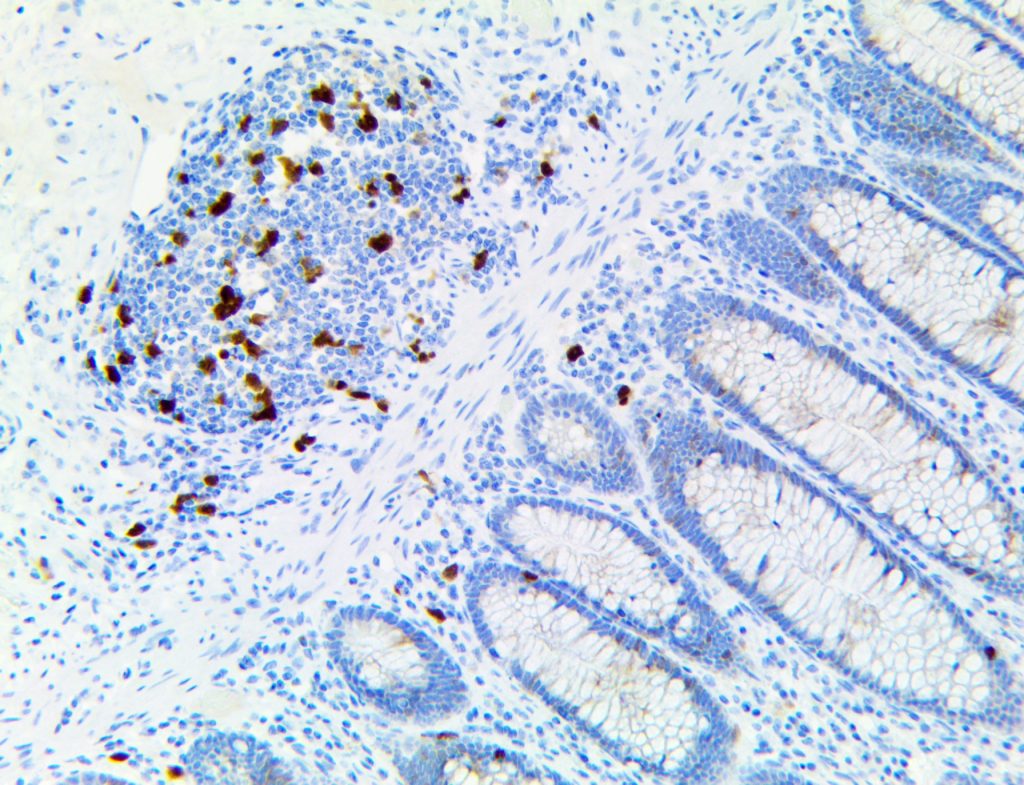

It is the ICU physician who is most likely to witness one of the deadliest manifestations of the abnormal immunological response, the cytokine storm syndrome (CSS). This response is also referred to by some as the cytokine release syndrome (CRS). CSS is characterized by continuous activation and expansion of macrophage and lymphocyte populations, which secrete large amounts of cytokines, causing the cytokine storm. This massive cytokine release is akin to hemophagocytic lymphohistiocytosis (HLH) disease, a syndrome characterized by initial unchecked and persistent activation of cytotoxic T lymphocytes and NK cells.

Clinical and laboratory manifestations of HLH include fever, enlarged liver and/or spleen, neurologic dysfunction, coagulopathy, liver dysfunction, cytopenias (i.e., low levels of erythrocytes, leukocytes, and/or platelets), hypertriglyceridemia, hyperferritinemia, hemophagocytosis, and eventually diminished NK cell activity as the immune system becomes progressively paralyzed. HLH can be familial (primary HLH) or secondary to another disease process (sHLH), such as rheumatic disease, in which it is referred to as macrophage activation syndrome (MAS, characterized by elevated ferritin).